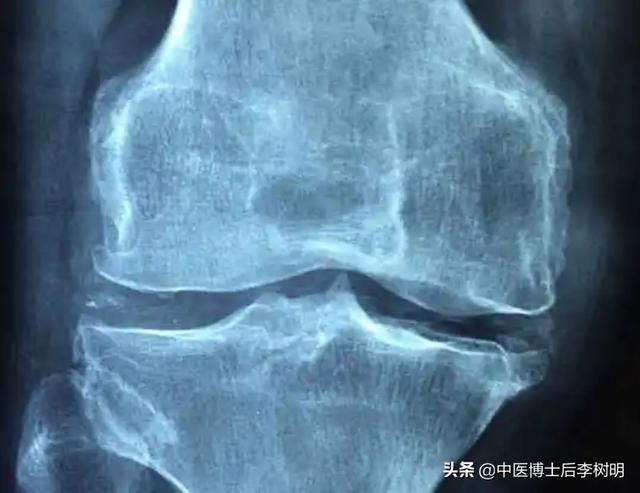

医生通过病史、体格检查和受影响关节的X光片来诊断骨关节炎。

在片子中,医生可以观察到关节的缝隙变窄了,靠近关节的骨头出现硬化,以及出现小空腔一样的囊性变。在关节的边缘周围有骨刺的形成。部分的病人还可以看到关节肿胀,以及关节内的游离体等等。